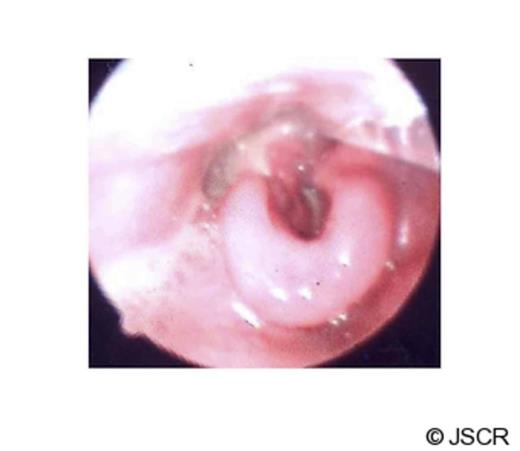

The patient was intubated in the theatre and direct laryngoscopy demonstrated an oedematous supraglottis with redundant patchy necrosis occluding the glottis. Subsequently he was transferred to Intensive Care Unit and treated conservatively with dexamethasone and antibiotics (Table 1). There was no improvement in the patient clinically or by laboratory parameters. Daily nasal endoscopy findings showed progressive supraglottic soft tissue oedema, worsening necrosis, pooling of saliva and diminishing air leak around the orotracheal tube.

On the same day, the patient was re-evaluated under general anaesthesia. Direct laryngoscopy revealed an extensive oedematous supraglottis with severe necrosis involving the laryngeal inlet, base of the tongue and right tonsillar bed. Incision of the soft tissue drained foul smelling fluid with minimal bleeding during biopsy. Surgical debridement was not possible without compromising the integrity of the larynx due to extensive necrosis. Subsequently a tracheotomy was performed with a limited exploration of the neck, showing only inflamed soft tissues in the anterior compartment. There was no evidence of necrosis or collection of pus in the neck spaces.